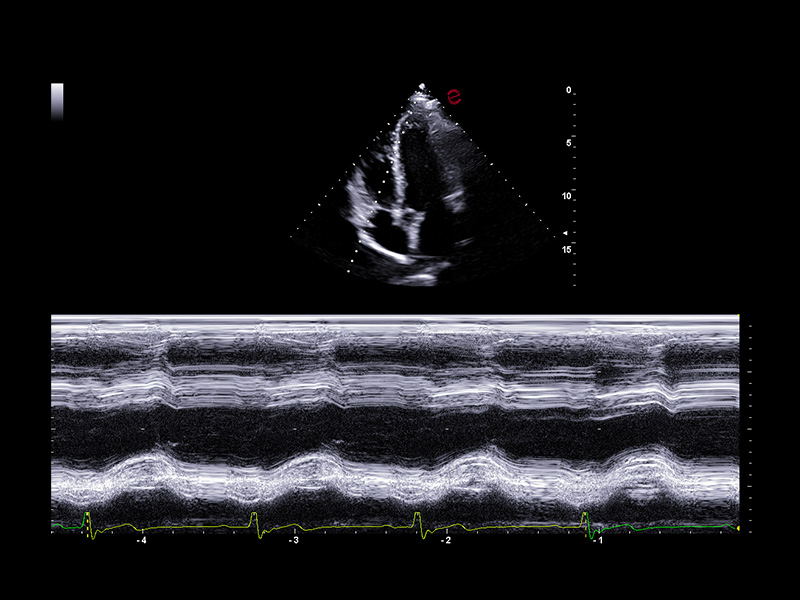

Outstanding image quality

Esaote’s XCrystal probe PX1-5 delivers exceptional clarity in B-mode imaging, providing deep penetration and excellent resolution even in technically challenging patients. Its advanced architecture ensures high Doppler sensitivity and spatial detail, enabling an accurate assessment of wall motion, valve morphology, and flow dynamics. From subtle endocardial borders to low-velocity diastolic flows, the PX1-5 probe ensures you never miss the details that matter.

Esaote’s cardiac ultrasound systems provide a full range of standard measurements for structural, functional, and hemodynamic evaluations, aligning with ASE/EACVI guidelines. From M-mode and 2D linear measurements to Doppler parameters, chamber quantification, and strain analysis, all tools are fully integrated for routine clinical use. Additionally, the platform supports customizable protocols and report templates, allowing clinicians to tailor workflows to specific patient populations, exam types, or institutional standards, thereby ensuring both diagnostic consistency and operational efficiency.